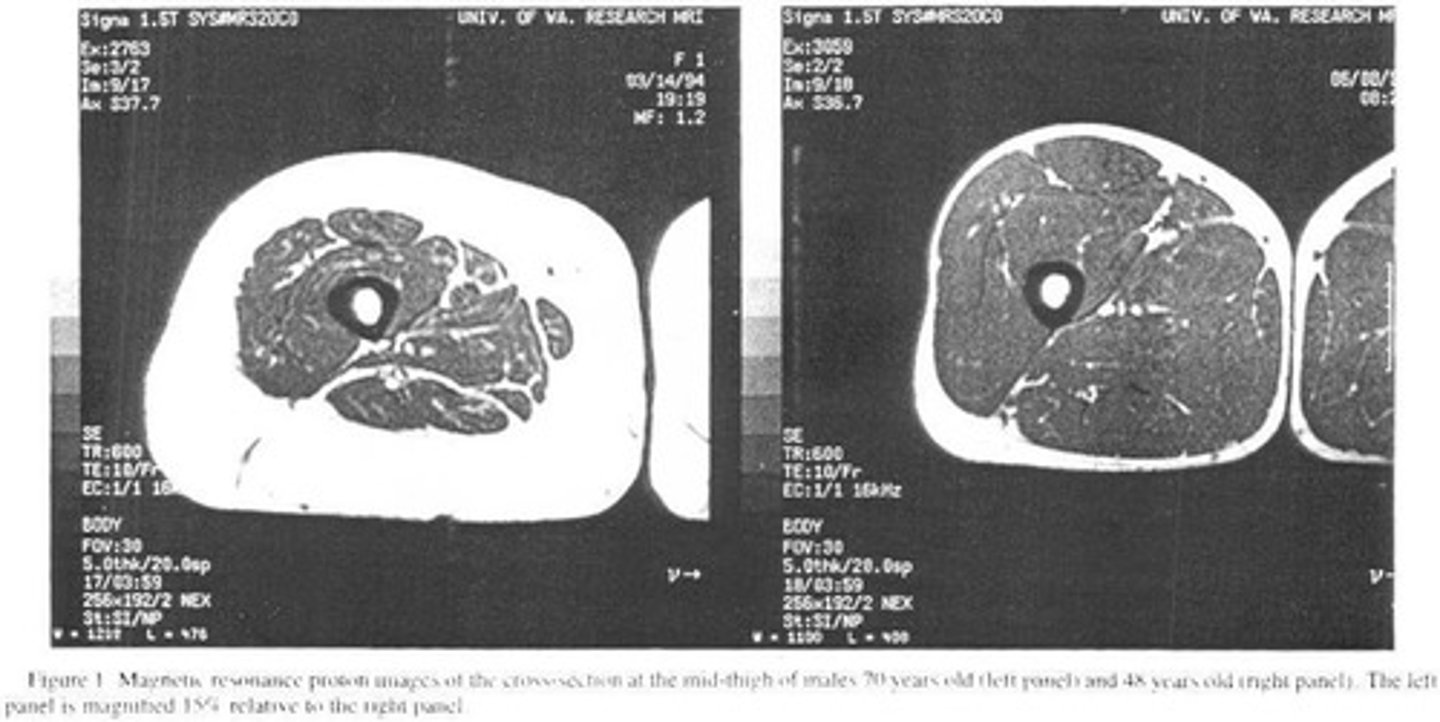

What happens to lean body mass (LBM) as one ages?

Decreased lean body mass; LBM decreases from 45% to 27% of total body weight.

What is sarcopenia?

Loss of skeletal muscle and strength associated with aging, with a loss of 0.5-1% per year after age 25.